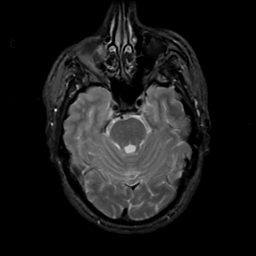

MR Study #6, March 17, 1991 -- Slice #15

[Home][Help][Clinical][Tour 1][Tour 2] Slice 15